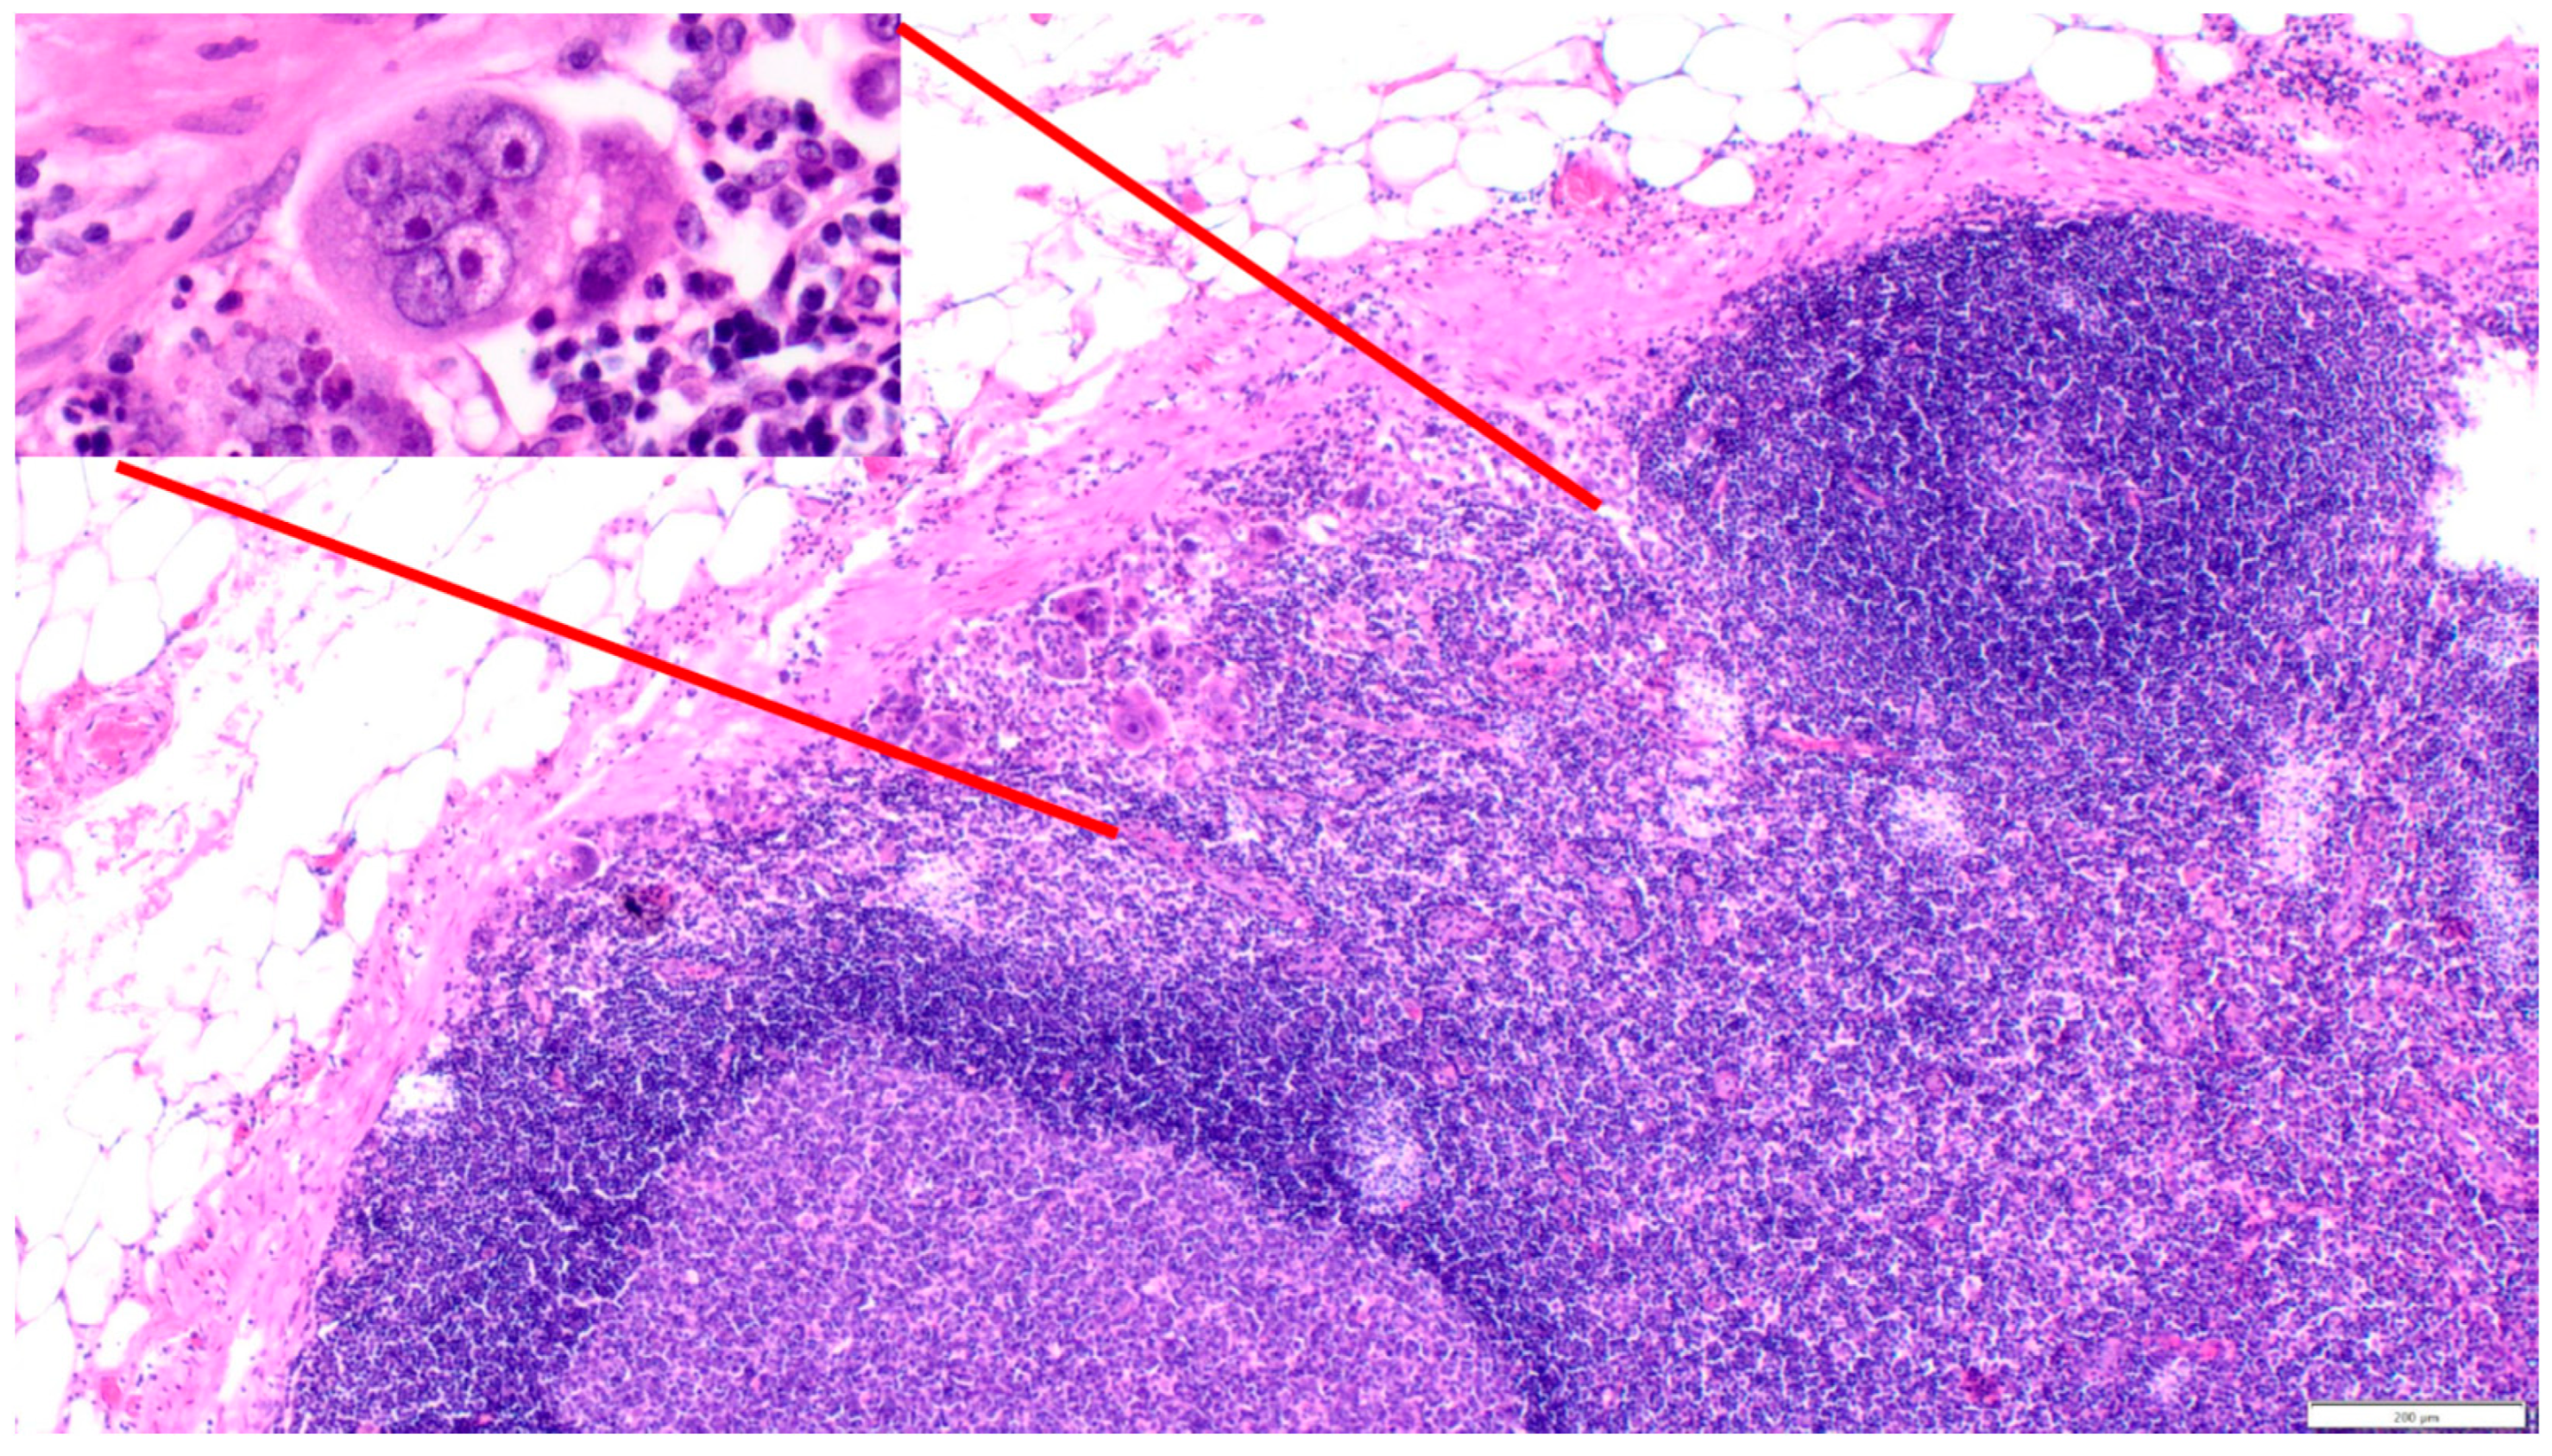

4. Polyploid Giant Cancer Cells—Dormant Locators or Migrating Pioneers